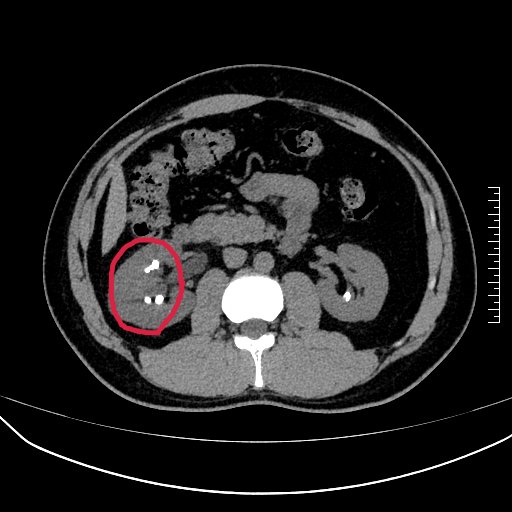

?單能CT:能顯示所有類型結(jié)石及其位置、大小。但它的局限在于難以準(zhǔn)確區(qū)分結(jié)石的具體化學(xué)成分;對尿酸結(jié)石診斷雖強(qiáng)于X線,但缺乏特異性生化信息。

普通CT拍出的腎結(jié)石